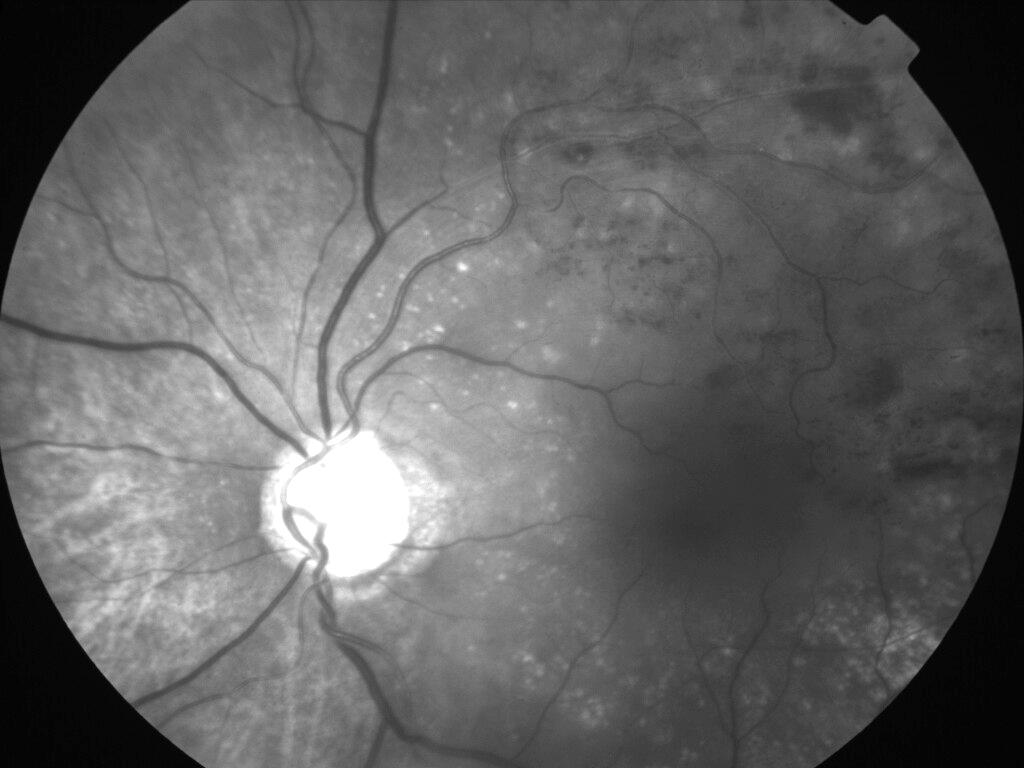

OCCLUSION DE BRANCHE DE LA VTS DE FORME ISCHEMIQUE MAJEURE